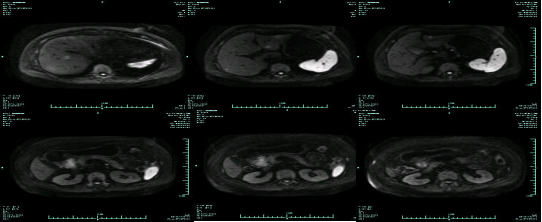

• MR示:

MR-H1

影像学检查结果评估:cPD。

• 第三次FOLFOX+T方案后 B超提示肝转移灶消失

疗效评估:cPR